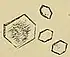

Struvite crystals found on microscopic examination of the urine

Laboratory investigations typically carried out include[56][65][58][68]

• microscopic examination of the urine, which may show red blood cells, bacteria, leukocytes, urinary casts, and crystals;